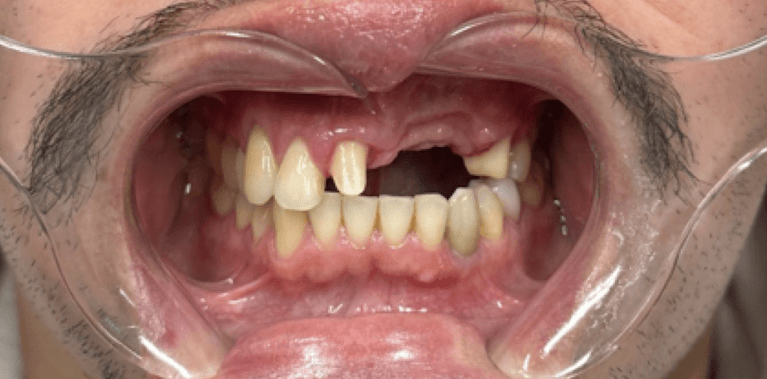

Broken Upper Central incisor with root canal replaced with Immediate implant after extraction.